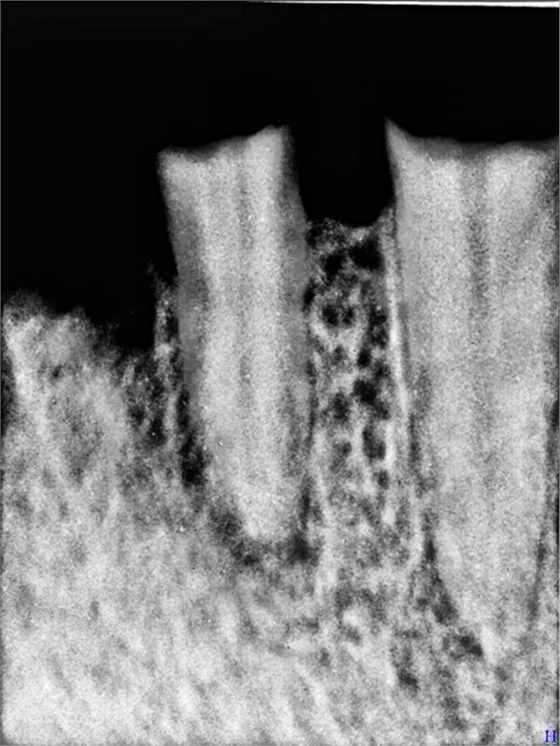

口腔檢查:22深齲有瘺管 23 24殘根,15近遠(yuǎn)中間隙(機(jī)械性片切造成),x片22 23 24 根尖低密度陰影

以上是口腔x片情況,由于患者把原義齒丟棄,沒有照片但看15號(hào)牙情況,義齒應(yīng)該體積不小